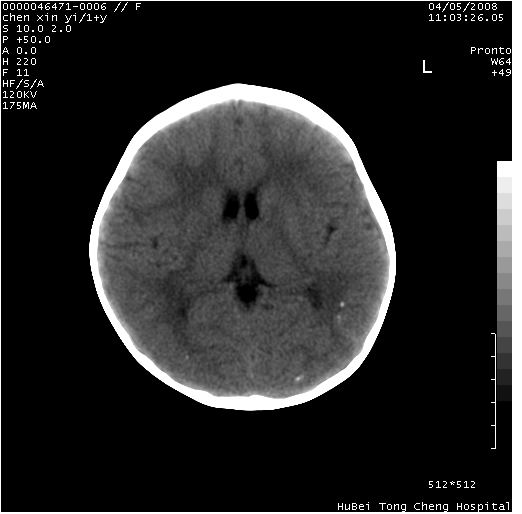

以下是引用zhangzhongshou在2008-4-9 12:54:00的发言:[br]请结合病史,有以下可能1、炎性肉芽肿钙化(含结核)2、寄生虫钙化(含脑囊虫)3、其他良性钙化性病变